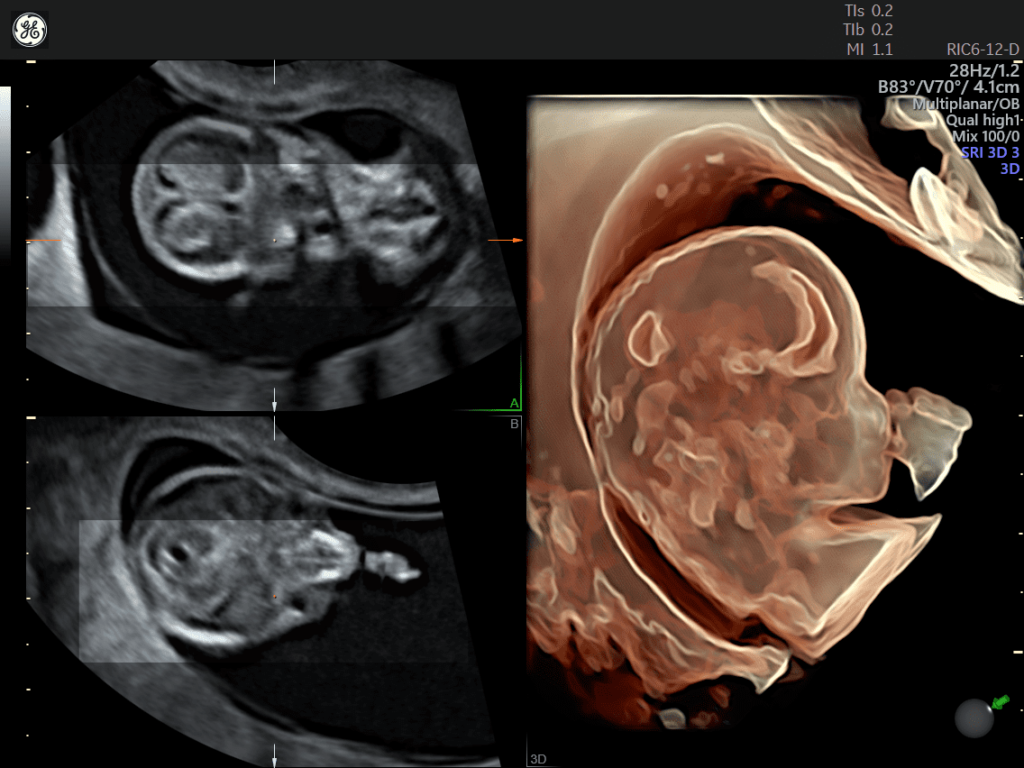

STIC: Per l’acquisizione 3D del cuore fetale, viene applicato un sofisticato algoritmo per la gestione e soppressione della distorsione causata dal movimento dei tessuti materni e fetali. Le immagini tomografiche sono riorganizzate in base alla fase del ciclo cardiaco e il data set 3D viene generato con solo immagini tomografiche nella stessa fase di ciclo cardiaco.

SonoVCAD Heart: strumento avanzato, basato sulla tecnologia Volume Ultrasound, CHE aiuta nella visualizzazione automatica delle scansione degli outflow cardiaci partendo dal volume data set acquisito. Permette una ricostruzione completa e automatizzata, relativa all’esame cardio fetale seguendo le linee guida delle società scientifiche AIUM, ACOG, ACR e ISUOG.

Semplicemente con due click il sistema è in grado di effettuare l’analisi e proporre le principali proiezioni.